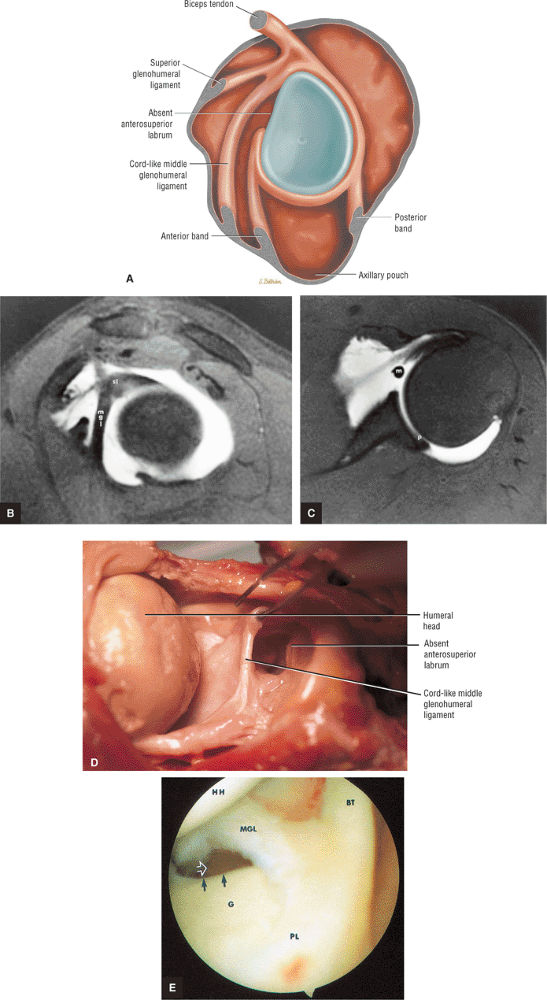

An anterior wedge labrum, which is characterized by a large anterior band of the IGHL that replaces or covers a small anterior labrum (e.g., the Buford complex) (Fig. 8.64)

-

The IGHL contributes to the anterior labrum through its anterior band. The anterior band may be prominent and overlay a small or even absent anterosuperior labrum as a normal variation.

The MGHL may be cord-like, absent, thin, or redundant on MR.